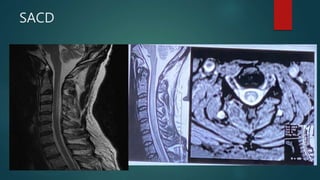

SACD

• #54 There is symmetric marked hyperintense signal intensity on T2/FLAIR imaging and restricted diffusion in the dentate nuclei, inferior cerebellar peduncles, lateral fourth ventricle floor in the expected locations of the vestibular tract and in the expected tract of the vestibular cochlear nerve. Also present, is diffusion restriction in the posterior columns of the proximal cervical cord, anteriorly in the inferior medulla, and punctate symmetric foci of restricted diffusion in the inferior colliculi of the quadrigeminal plate and medial geniculate bodies. There is mild high signal on FLAIR and diffusion weighted imaging involving the bilateral putamen 2nd image is dwi image